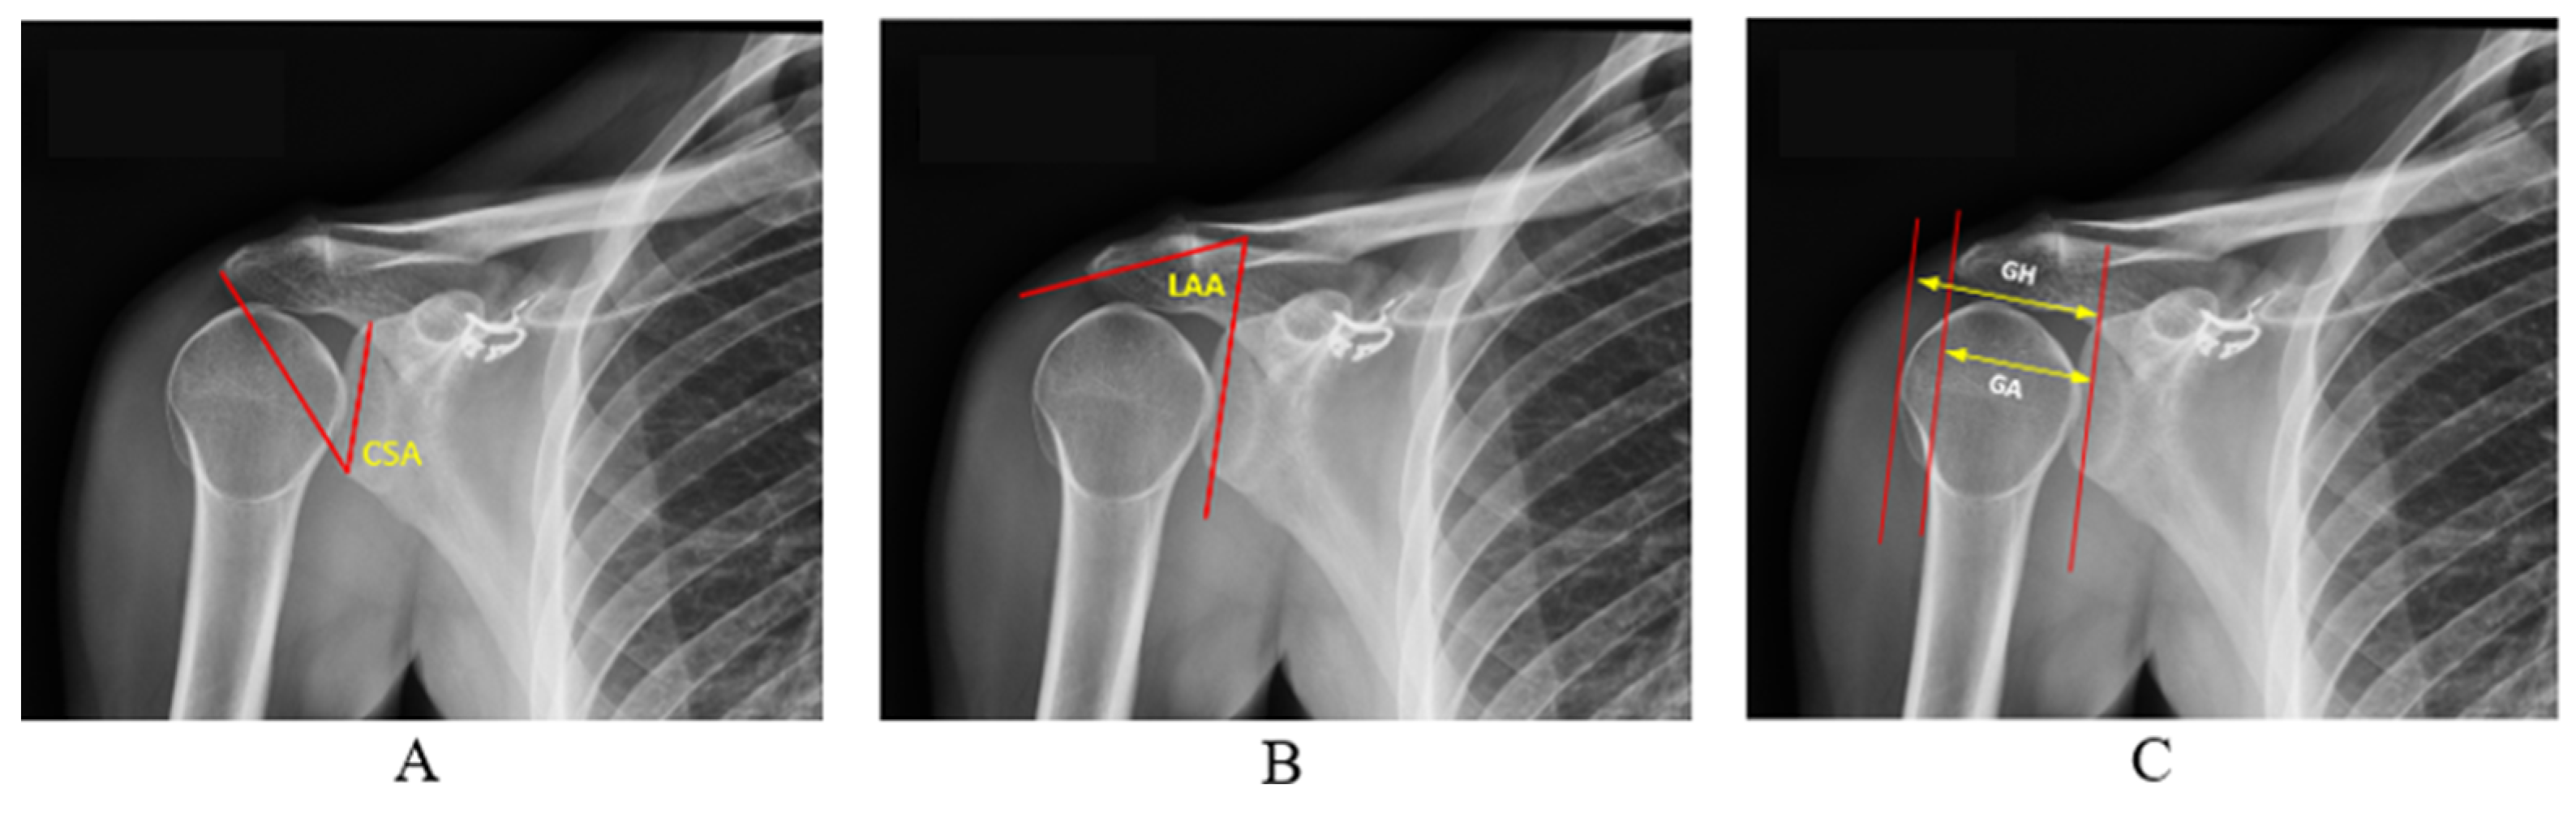

As shown in Figure 2, three different radiographic measurements were derived using these boundary pixels: CSA, AI, and LAA.

At this stage, the edge pixels of the segmented glenoid, acromion, and humerus were obtained. Using these edge pixels, the measurements for CSA, AI, and LAA were calculated. For the CSA measurement, we first defined the upper part of the glenoid (G) as the point where the upper edge of the glenoid fossa intersects with a vertical line. Similarly, the lower part of the glenoid (I) is defined as the point where the lower edge intersects with the same vertical line. The lateral edge of the acromion (A) is the outermost point of the acromion. Following these definitions, a vertical line is drawn from the upper part to the lower part of the glenoid (G-I line). Let the slope of this line be m 1 . Then, another line is drawn from the lower part of the glenoid (I) to the lateral edge of the acromion. Let the slope of this line be m 2 . The CSA is the angle between these two lines, mathematically expressed as in Equation (6).

AI is defined as the ratio of the distance between the glenoid fossa and the lateral edge of the acromion (GA) to the distance between the glenoid edge and the lateral surface of the humeral head (GH). Its mathematical expression is given in Equation (7)

Let the slope of the line GA, drawn between a point on the glenoid cavity and a point on the lateral edge of the acromion, be n 1 , and the slope of the line GH, drawn from the glenoid cavity to the head of the humerus, be n 2 . The lateral acromial angle is the angle formed by the intersection of these two lines. Its mathematical expression is given in Equation (8).

Figure 2. Representation of CSA (A), LAA (B), and AI (C).